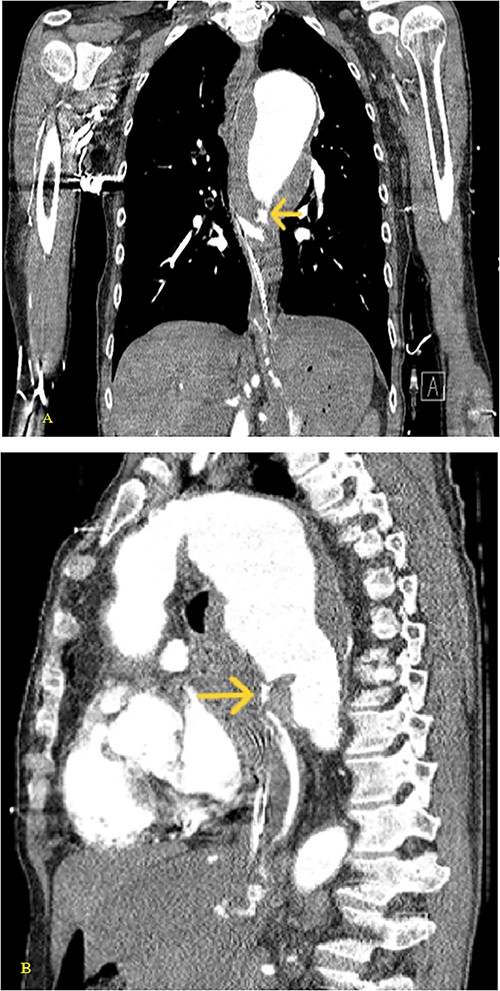

(A–D) Coronal CT chest with contrast reveal the descending aortic aneurysm of at least 6.5-cm diameter. Deep ulceration in the descending aorta at approximately the level of the pulmonary artery bifurcation. The ulceration has eroded into the esophagus. Extravasation of contrast is observed from the ulceration into the esophagus.